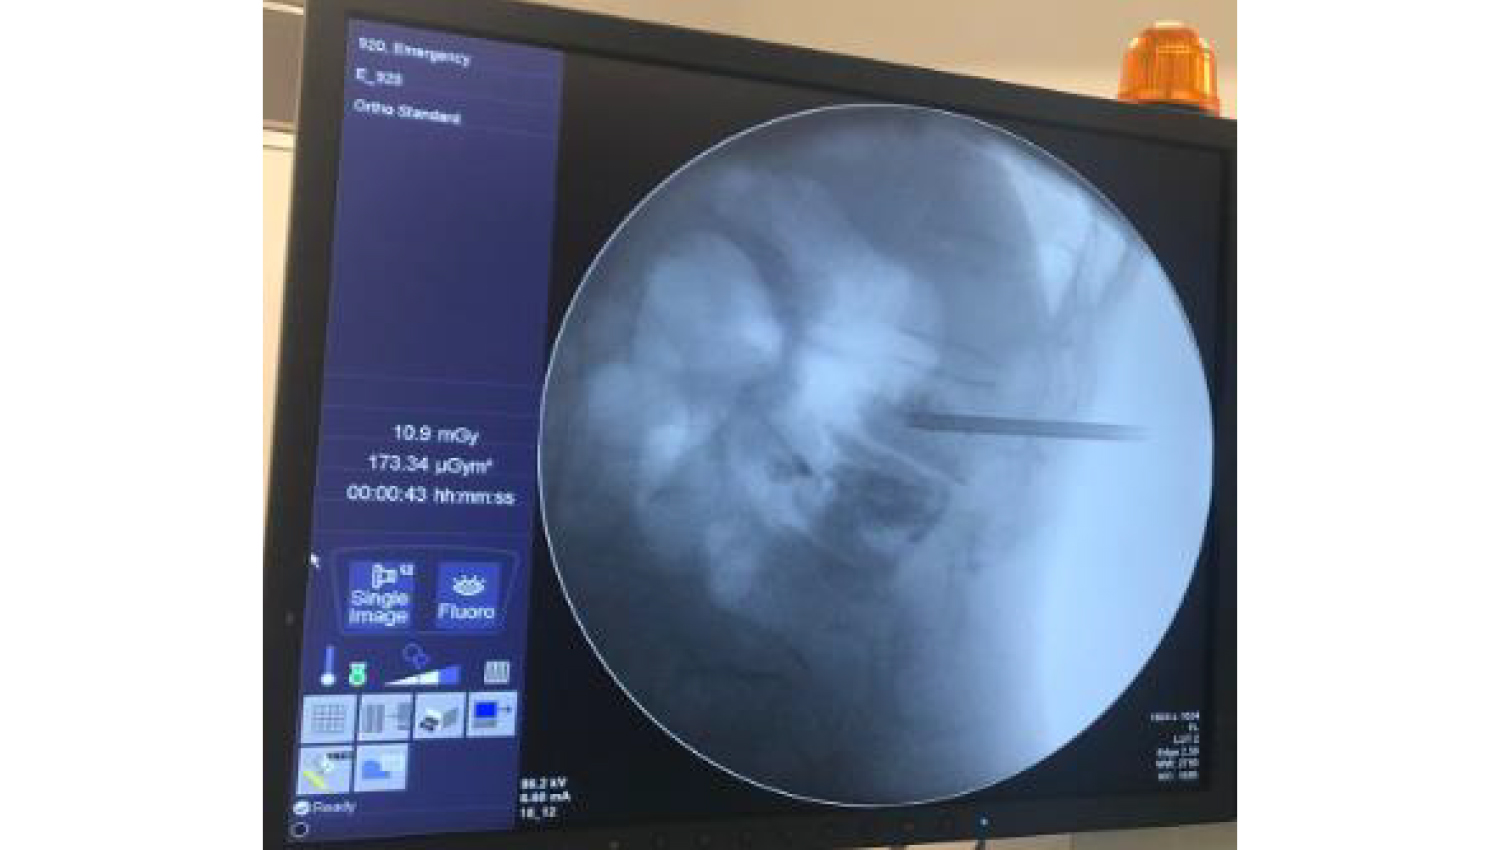

2.Imaging of the defect in the spine at the beginning of the operation.

3.The Powerbone Bone Cement LV20 preparation process has been completed and the Bone Cement Applicator Kit, which is a Bone Filler and Pusher Cannulated Screw, has been filled for application.

4.Bone Filler and Pusher Cannulated Screw waiting in the prepared state are prepared to be applied to the defect area. With the application of Bone Cement, the change in imaging is observed.